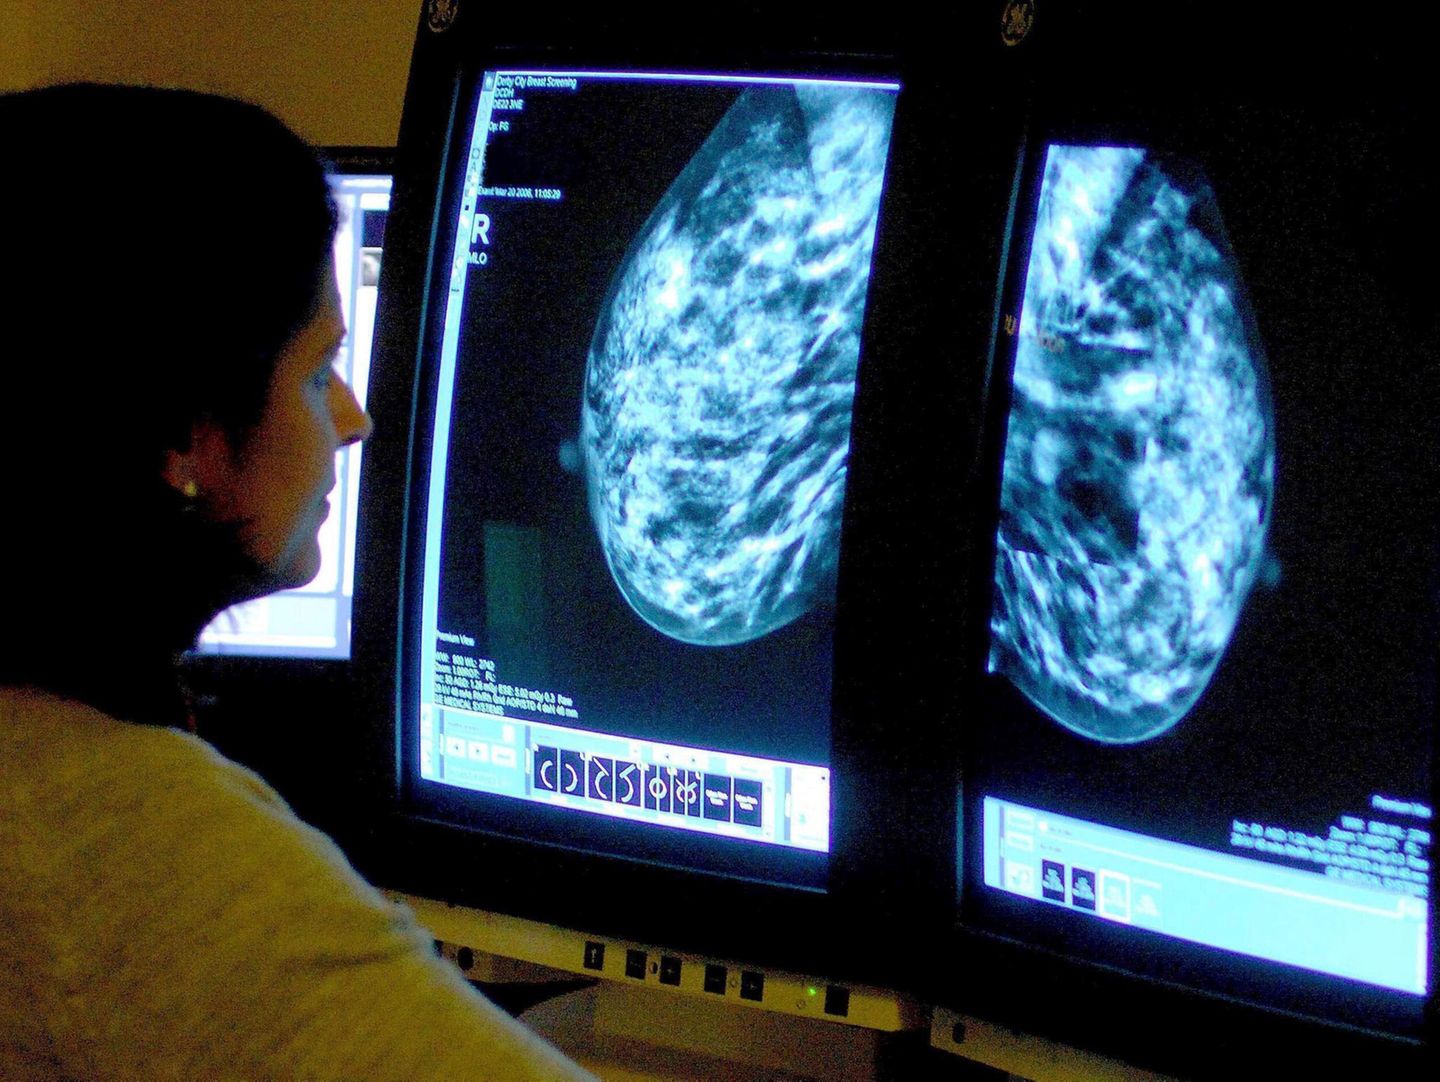

In den USA soll Brustkrebs jetzt durch die Früherkennung mit der Mammografie rechtzeitig erkannt und behandelt werden können

© Rui Vieira / Picture Alliance